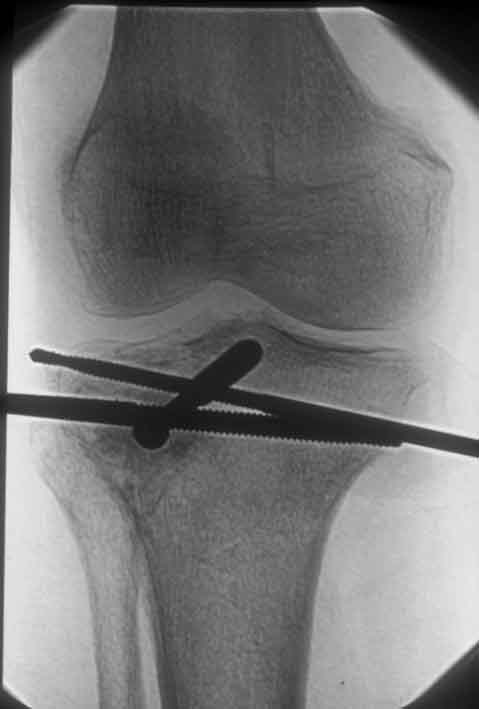

Tibiakopffraktur mit tiefer Impression (Schichtaufnahme) Anheben der Fraktur, Unterfütterung mit allogenem Knochen, minimalinvasive Stabilisierung mit Spongiosaschrauben, neutralisieren der Fraktur mit Hoffmann II Fixateur (freie Pinplazierung)

Hoffmann II Montage mit freier Pinplazierung proximal. Wenige Tage nach der Operation besteht freie Beweglichkeit im Kniegelenk Befund 8 Wochen nach der Operation, der Fixateur kann entfernt werden.